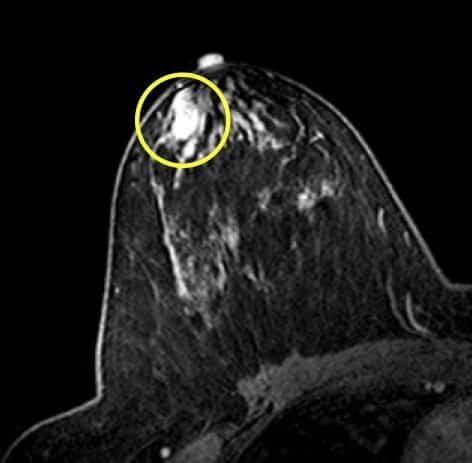

الوَرَم الحُلَیمي القَنَوي Duct papilloma

الوَرَم الحُلَیمي القَنَوي Duct papilloma: وھو ورمٌ حميد

داخل قَناة الثدي (الأنبوب الذي ينقل الحلیبَ من الغدَّة إلى

الحلمَة)، يسبِّب سیلان الحلمة (نَجیجُ الحلمة) مُدمَّى من

ثديٍ واحد عادة ويجب استئصاله للخوف من تحوله لورم خبيث.

2- الورمُ الحلیمي ورمٌ يُشبِه الثؤلولَ، يَقیس حوالي 1 – 2 سم

عادة، ويوجد داخِل واحدة من قنوات الثَّدي، حیث تحمل قَنواتُ

الثدي الحلیبَ من الغدَّة إلى الحلمة.

تصوير الثدي الشعاعى (الماموجرام) Mammography